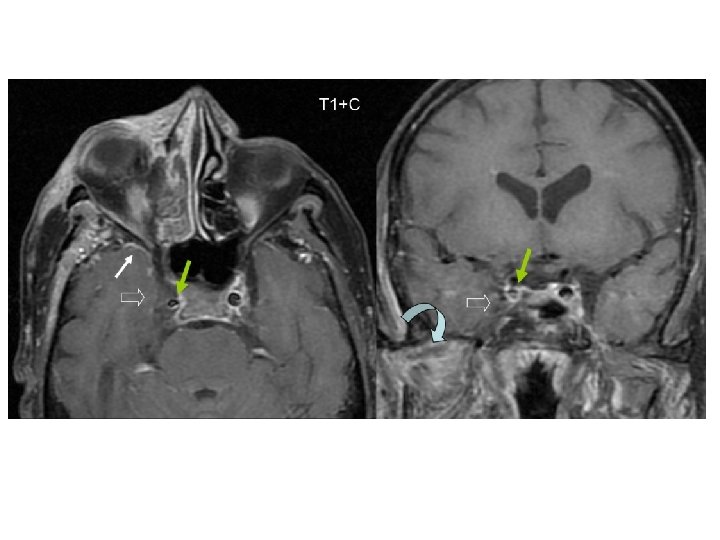

Cavernous Sinus Thrombosis Symptomatology • Orbital pain • Proptosis and chemosis • Ophthalmoplegia • Symptoms in contralateral eye • Associated with sepsis and meningismus Radiology • Poor venous enhancement on CT • Better visualized on MRI

• Meningitis • Epidural abscess • Subdural abscess • Intracerebral abscess • Cavernous sinus, venous sinus thrombosis

• Uncommon, frontal and frontoparietal lobes • Generally from frontal sinusitis • Sphenoid • Ethmoids • Mortality 20 -30% • Neurologic sequelae 60%

• • • Subdural Abscess Generally from frontal or ethmoid sinusitis Third-most common intracranial complication, rapid deterioration Mortality in 25 -35% Residual neurologic sequelae in 3555% Accompanies 10% of epidural abscesses